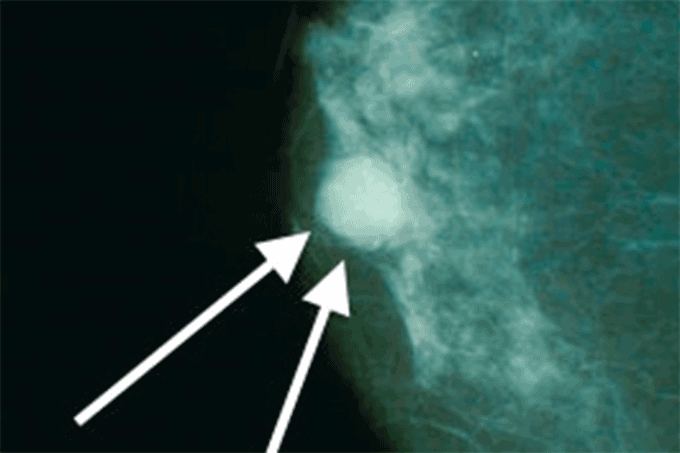

Câncer de mama: Dispositivo desenvolvido por pesquisador da UFSCar recebe menção honrosa no Prêmio Mercosul de Ciência e Tecnologia  (Bakerstmd/Wikimedia Commons)